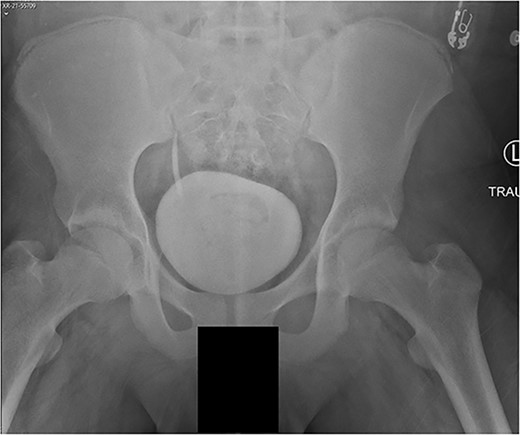

A 14-year-old boy sustained closed right and left mid-shaft femur fractures (Right OTA 32-A3, Left OTA 32-B2) after an all-terrain vehicle accident (Fig. 1a and b). The patient was classified as obese with a BMI of 37. Bone age was determined to be approaching skeletal maturity and so a rigid trochanteric entry femoral rod was selected for the implant [15, 16] (Fig. 2). Laboratory derangement included hyperphosphatemia and hypoalbuminemia. Therefore, additional measures to include early fracture stabilization and the RIA adjunct was selected for our patient [17].

(a) Right femur fracture (OTA 32-A3). (b) Left femur fracture (OTA 32-B2).